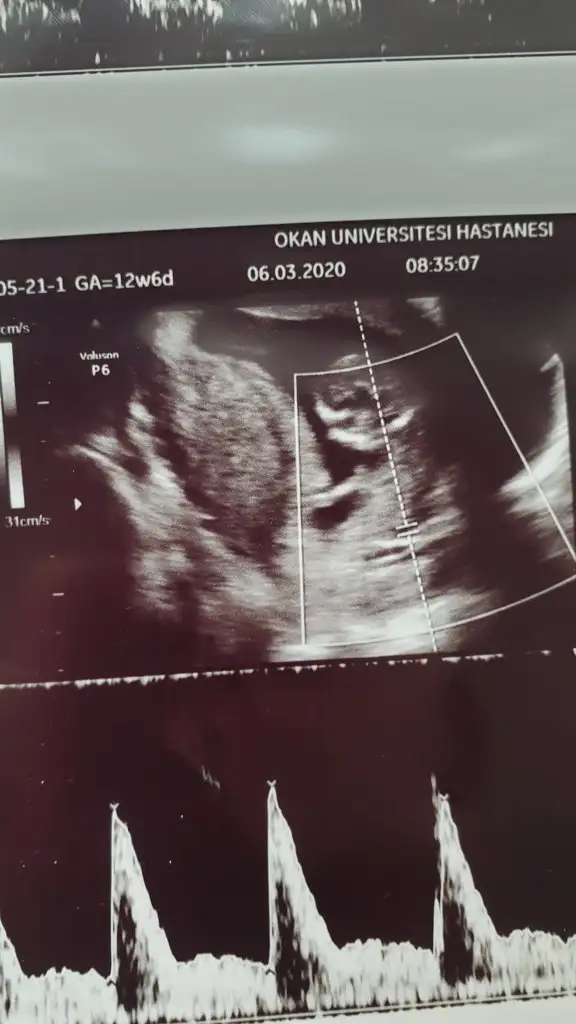

Kız gibiIkra meyra tekrar usg paylaşın demiştiniz sat a göre 12+1 ultrasona göre 12+6 çıktık ❤Pazartesi tekrar gideceğim ama bunu da atmak istedim belki bir tahmin olur

![]()

11 12 13 haftalar nub için uygun şimdilik sanki erkek gibi gibi dediğimiz usgleri paylaşırmısınızIkra meyra bir bakarmısın canım